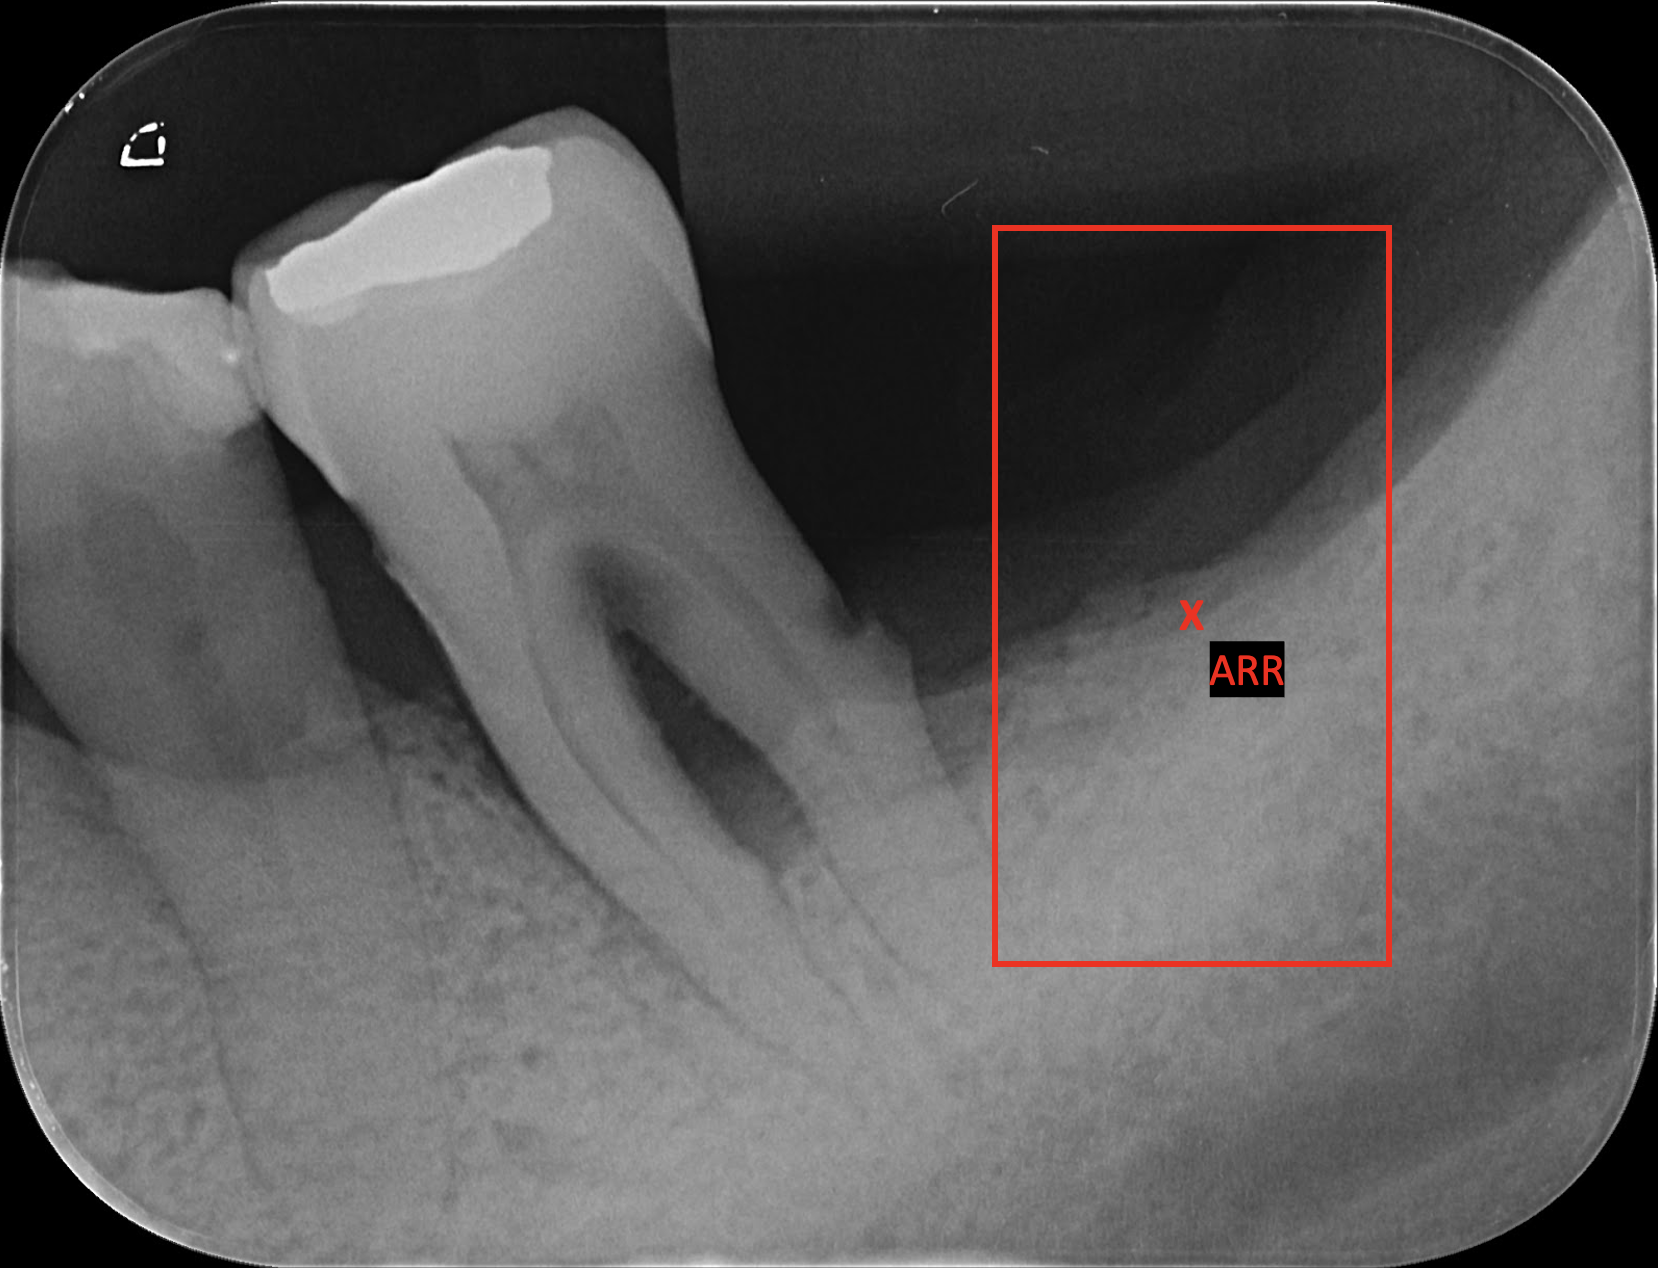

We conducted comprehensive annotation of the collected radiographs, divided into four steps. These include annotating Bone Level Keypoints (BLK) for each tooth, identifying the Teeth Bounding Box (TBB) with tooth orientation, annotating ARR keypoints, and widened PLS bounding boxes. Figure 1 provides visual examples of the annotations.

Refer to caption

Figure 1: Three images containing example annotations of the collected keypoints and rotating bounding boxes. Left: single root and double root tooth with example bone loss keypoints and tooth box annotations. Middle: double root tooth with example widened periodontal ligament space bounding box. Right: missing tooth with example ARR keypoint and bounding box.

Alveolar Ridge Resorption (ARR)

In the ARR annotation step, focus is placed on identifying the areas of Alveolar Ridge Resorption. This involves annotating the current bone level at locations where a tooth is missing and bone resorption has begun. Annotations for ARR are completed as a bounding box indicating the missing tooth area and a keypoint indicating the lowest point of ARR within the localised area of the missing tooth.